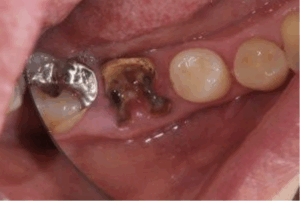

これは、神経まで到達してしまった虫歯C3(シースリー)です。

冷たいもの、温かいものまでもひどくしみて痛みます・・・

歯が欠けてしまったり、何もしなくてもズキズキ痛みます。

歯医者では、歯の神経を取る治療がスタートします。

こうなってしまうと、二度と自分の健康な歯は戻ってきません💧

ほとんど歯が残っていない虫歯C4(シーフォー)

歯がほとんど失われ、根っこの部分だけが残っている状態。

強い痛みがあったのに、急に痛まなくなった場合は

歯髄壊死といい、完全に組織か死んでしまって痛みを感じなくなります。

治療法は、残っている根っこを抜いて

→ブリッジ・入れ歯・インプラントの3つの選択肢になります。